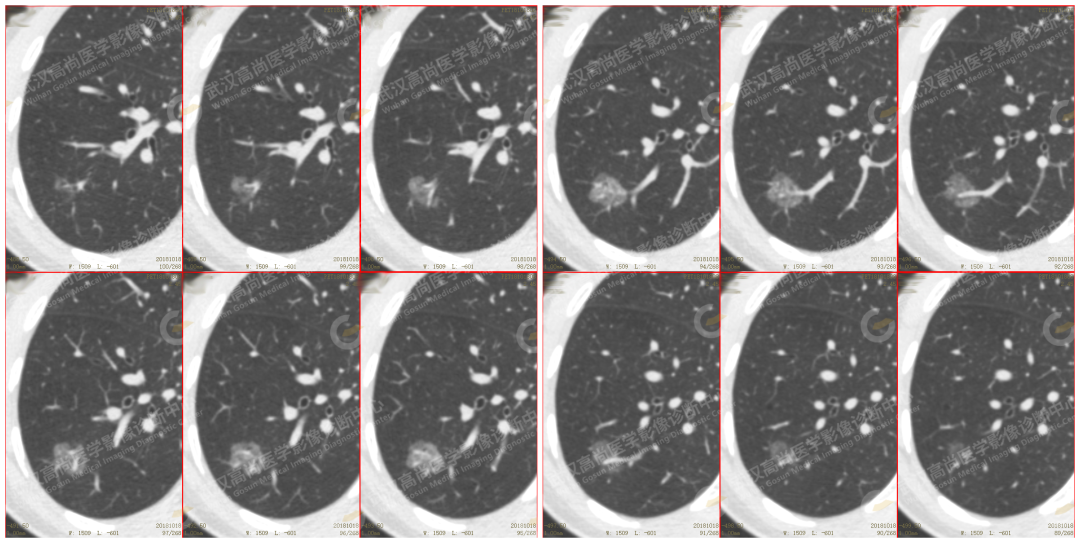

左肺上叶尖后段 2 个混合磨玻璃结节(mGGN):SUVmax 分别为 2.0 、09 SUVmin 分别为 1.5、0.8

CT 示:混合磨玻璃结节,中央密度较高,边缘清楚,形态不规则,见分叶、毛刺及血管集束征,其内见血管穿行其中